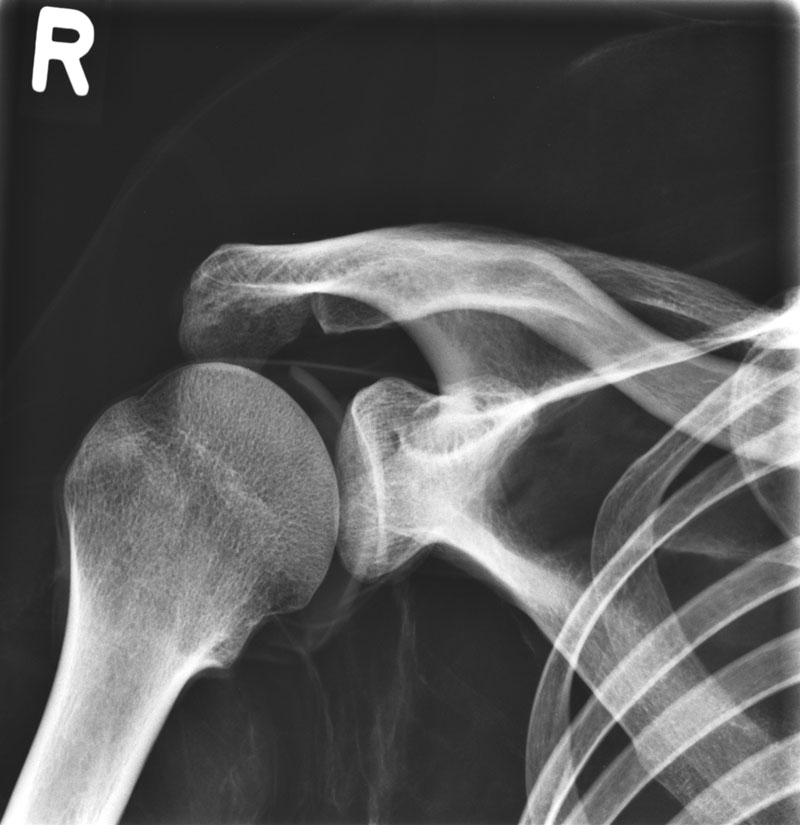

北京睿志科技發(fā)展有限公司、北京瑞森科技發(fā)展有限公司銷售的:德國QUART-12731德國X/CT全身可動體模(德國全身X射線CT醫(yī)學影像模體)用于醫(yī)學影像技術教學和X線機器和CT機器的質量檢查,x線機的校正以及低線量研究等,在普放設備與CT下都能得到與真實人體高度相似透視圖像,并且支持3D影像重建。將用于影像檢查教學,訓練技師,圖像質量管理等多種用途。

德國QUART-12731X/CT全身可動體模(德國全身X射線CT醫(yī)學影像模體)是世界上僅有的一款采用歐洲/亞洲人骨骼手工制作而成(因為采用歐洲/亞洲人骨骼手工制作而成,所以每個德國X/CT全身可動體模(德國全身X射線CT醫(yī)學影像模體)的身高、重量不完全一致),人工材料逼真的心臟、肺、吼和腎臟??苫顒雨P節(jié)實現拍X射線培訓或科研應用時的基本定位,無金屬部件或液體結構。

*2、全身XCT教學模體、真人骨骼,人工材料逼真的心臟、肺、吼和腎臟等;

*7、滿足任意部分進行X/CT掃描,成像效果與真實人體一致,影像片中能正常分辨出骨齡。